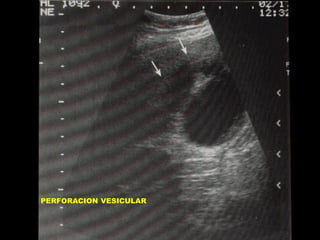

PERFORACION VESICULAR

•

COMPLICA 2 A 19% DE COLECISTITIS

MORTALIDAD: 19 A 24%

3 A 7 DIAS DE INICIO DE SINTOMAS

MECANISMO: OBSTRUC. DE CISTICO, DIS –

TENSION, ISQUEMIA DE FUNDUS, PERFORACION.